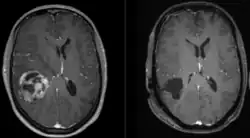

![]() | |

| A coronal view (from the back of the head) of a contrast-enhanced MRI revealing a glioblastoma in a 15-year-old boy | |